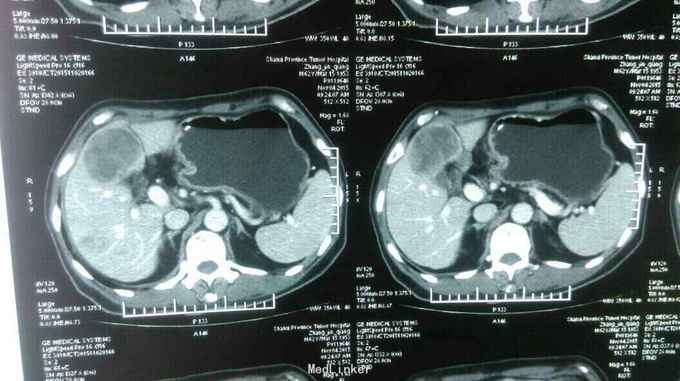

患者:男,62岁,主 诉:残胃癌多发转移化疗后,恶心呕吐5月余。 现病史:患者于2014年9月份自觉进食后上腹部饱胀感,就诊于忻州市人民医院,胃镜提示:胃大部切除术后,吻合口大弯侧粘膜隆起,充血,水肿,伴糜烂,质 脆,易出血,于2014年9月23日就诊于中国医学科学院肿瘤医院,诊断残胃癌,中分化腺癌,全腹部示CT提示:胃远端呈术后改变,吻合口扩张不良,吻合口壁厚,吻合口周围、胃左区新发现多发不均匀结节,大者短径约1.6cm;腹腔肠系膜根部、腹膜后多个小淋巴结;肝脏新出现多发结节,大者直径约1.5cm,考虑转移,盆腔少量积液。于2014年11月15日行XELOX方案化疗一周期,具体用药:奥沙利铂150mg,d1希罗达1500mg早 2000mg晚d1-d10,14天重复一次。后于忻州市人民医院2014年11月至2015年01月给予XELOX 方案化疗全身化疗5周期,化疗第二周期后,患者上腹部饱胀感减轻。于2015年3月12日就诊山西省肿瘤医院,全腹部CT提示胃腔缩小,残胃壁增厚,最后处约1.9cm,,残胃下方系膜内一枚囊性结节,大小约2.9X2.3cm,转移不除外:肝脏S8段一枚低密度灶,大小约为0.6X0.4cm;右肺中叶结节,大小约为1.6X1.4cm,肝脏S8段动脉期环形强化结节,考虑转移,右肺中叶炎性病变,继续给予行XELOX方案化疗2周期(奥沙利铂200mg,卡培他滨1.5g/次,2次/日,共14天)。因骨髓抑制明显,于2015年5月4日入该院后给予卡培他滨化疗一周期(卡培他滨2g/次,2次/日,共计14天)。2015年6月10日入该院复查CT提示肝内多发低密度影,部分新增,右肺中叶局限性肺不张,纵膈内多发小淋巴结,给予更换TP方案化疗一周期(多西他赛120mg,顺铂90mg),治疗结束于6月25日出院。出院后患者间断出现恶心、呕吐,于7月13日入该院复查胸腹部CT:残胃壁局部略变薄;头颅核磁未见异常。患者体质较差,不能耐受化疗,于7月21日始口服阿帕替尼250mg/日治疗。后患者间断出现恶心、呕吐,呕吐物为胃内容物,8月底患者停服阿帕替尼。9月8日入该院复查提示:肝脏多大转移增大,患者恶心、呕吐明显,予以留置鼻饲营养管,行EOF化疗一周期,共计用药:奥沙利铂150mg,表柔比星50mg,氟尿嘧啶3.0g,化疗所致骨髓抑制Ⅱ度。2015-11-02再次入住山西省肿瘤医院给予康莱特静点等对症治疗9天。目前患者每日鼻饲饮食后呕吐7-8次,每次呕吐量约40-50ml左右,全身疲软,精神食欲差,睡眠尚可,大便3-4日一次,较干结,小便基本正常,近3月体重下降约5kg。 既往史:既往患者高血压病史15年余,最高血压达180/100mmHg,平素口服尼福达片1片/日降压治疗,血压控制尚可;2型糖尿病10年余,曾皮下注射诺和灵30R控制血糖,近1月因进食量减少,已停用胰岛素治疗;40年前因“十二指肠穿孔”行胃大部除术;5年前山西医科大学第二医院确诊右半结肠癌行右半结肠切除术;10年前曾行阑尾切除术

诊断: 中医诊断: 胃癌 痰气交阻 西医诊断:残胃癌 中分化腺癌 浸润型 Lauren分型:肠型 肝转移 胃周 腹腔淋巴结转移 多疗程化疗后 空肠营养管植入术后: 呕吐原因待查 中度贫血 右半结肠癌(术后、化疗后) 2型糖尿病 治疗:入院给予查腹部立位片未见液气平面,给予止吐,输血纠正贫血,营养支持,中医中药扶助正气治疗,行动脉介入化疗药灌注(奥沙利铂150mg+氟尿密啶0.75g),肝转移灶(吡柔比星20mg+碘化油6ml)栓塞治疗。